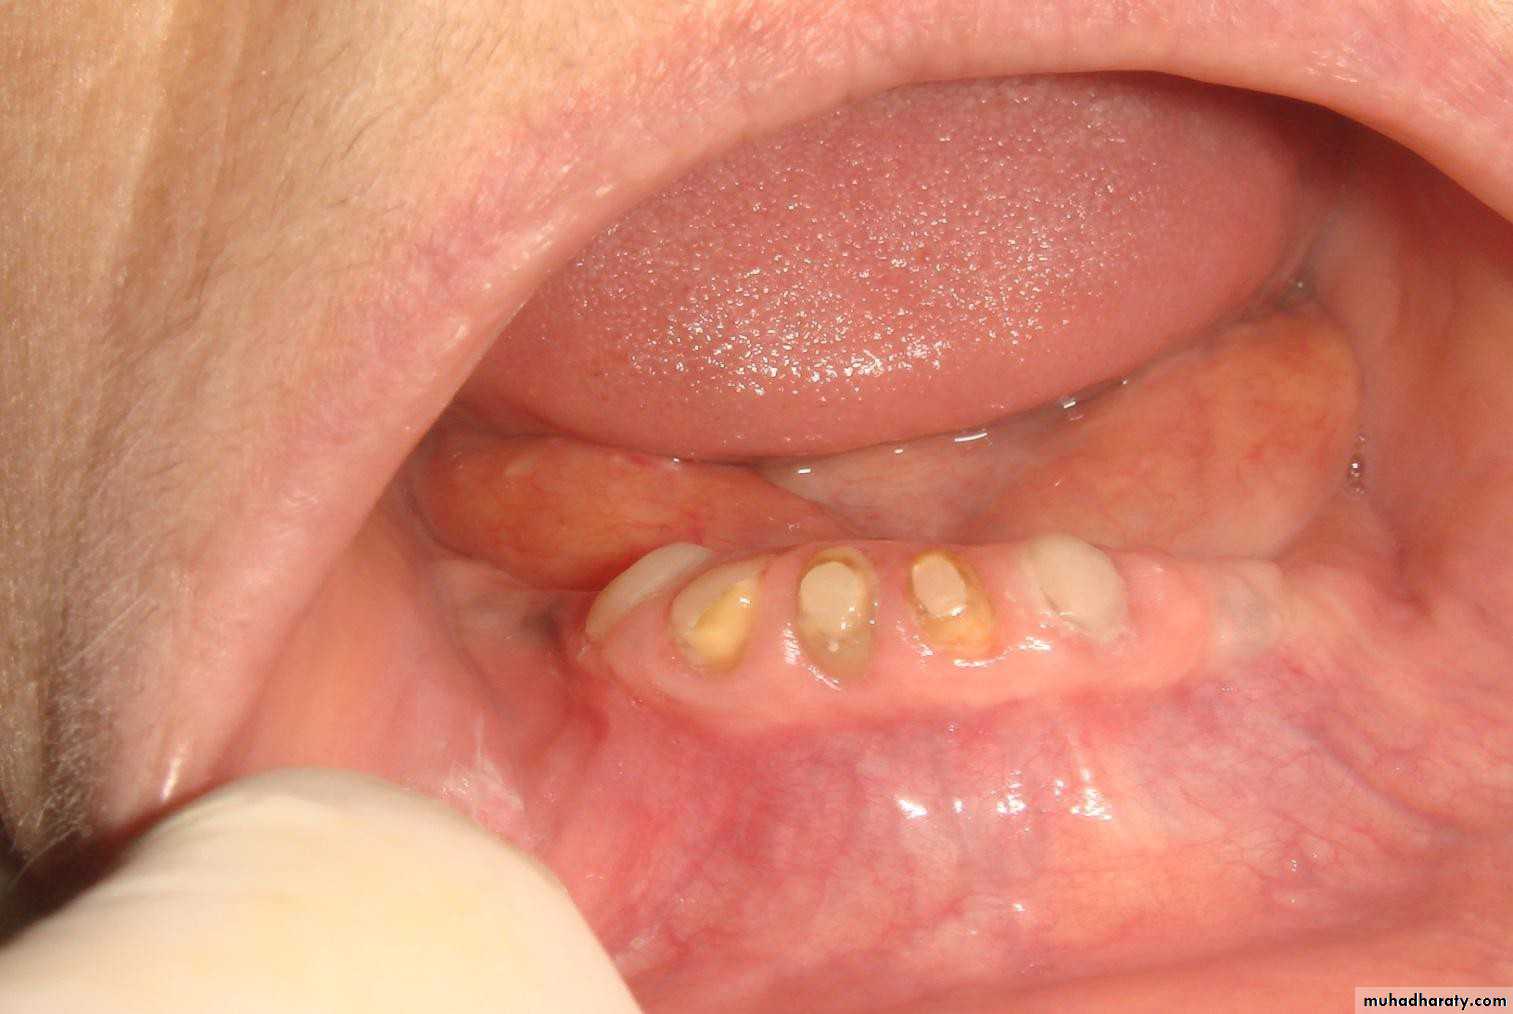

• 1- Simple tooth modification of vital abutment.

• A- Thimble-shaped